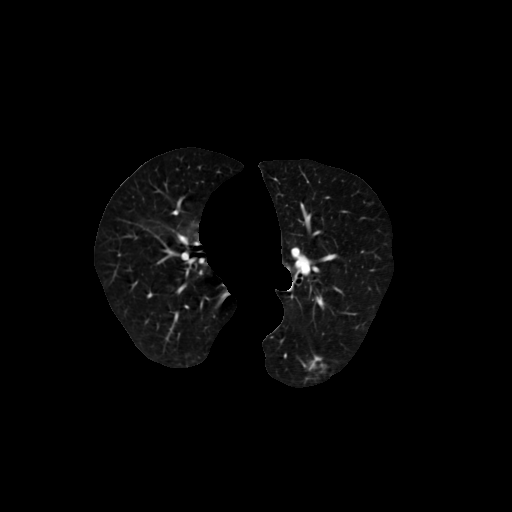

效果:

def get_segmented_lungs(im):

'''

对输入的图像进行肺部区域分割,提取有效的肺部区域,用于模型训练

:param 输入的图像

:return: 返回分割结果

binary = im < -400 # Step 1: 转换为二值化图像

cleared = clear_border(binary) # Step 2: 清除图像边界的小块区域

label_image = label(cleared) # Step 3: 分割图像

areas = [r.area for r in regionprops(label_image)] # Step 4: 保留2个最大的连通区域

areas.sort()

if len(areas) > 2:

for region in regionprops(label_image):

if region.area < areas[-2]:

for coordinates in region.coords:

label_image[coordinates[0], coordinates[1]] = 0

binary = label_image > 0

selem = disk(2) # Step 5: 图像腐蚀操作,将结节与血管剥离

binary = binary_erosion(binary, selem)

selem = disk(10) # Step 6: 图像闭环操作,保留贴近肺壁的结节

binary = binary_closing(binary, selem)

edges = roberts(binary) # Step 7: 进一步将肺区残余小孔区域填充

binary = ndi.binary_fill_holes(edges)

get_high_vals = binary == 0 # Step 8: 将二值化图像叠加到输入图像上

im[get_high_vals] = -2000

print('lung segmentation complete.')

return im, binary